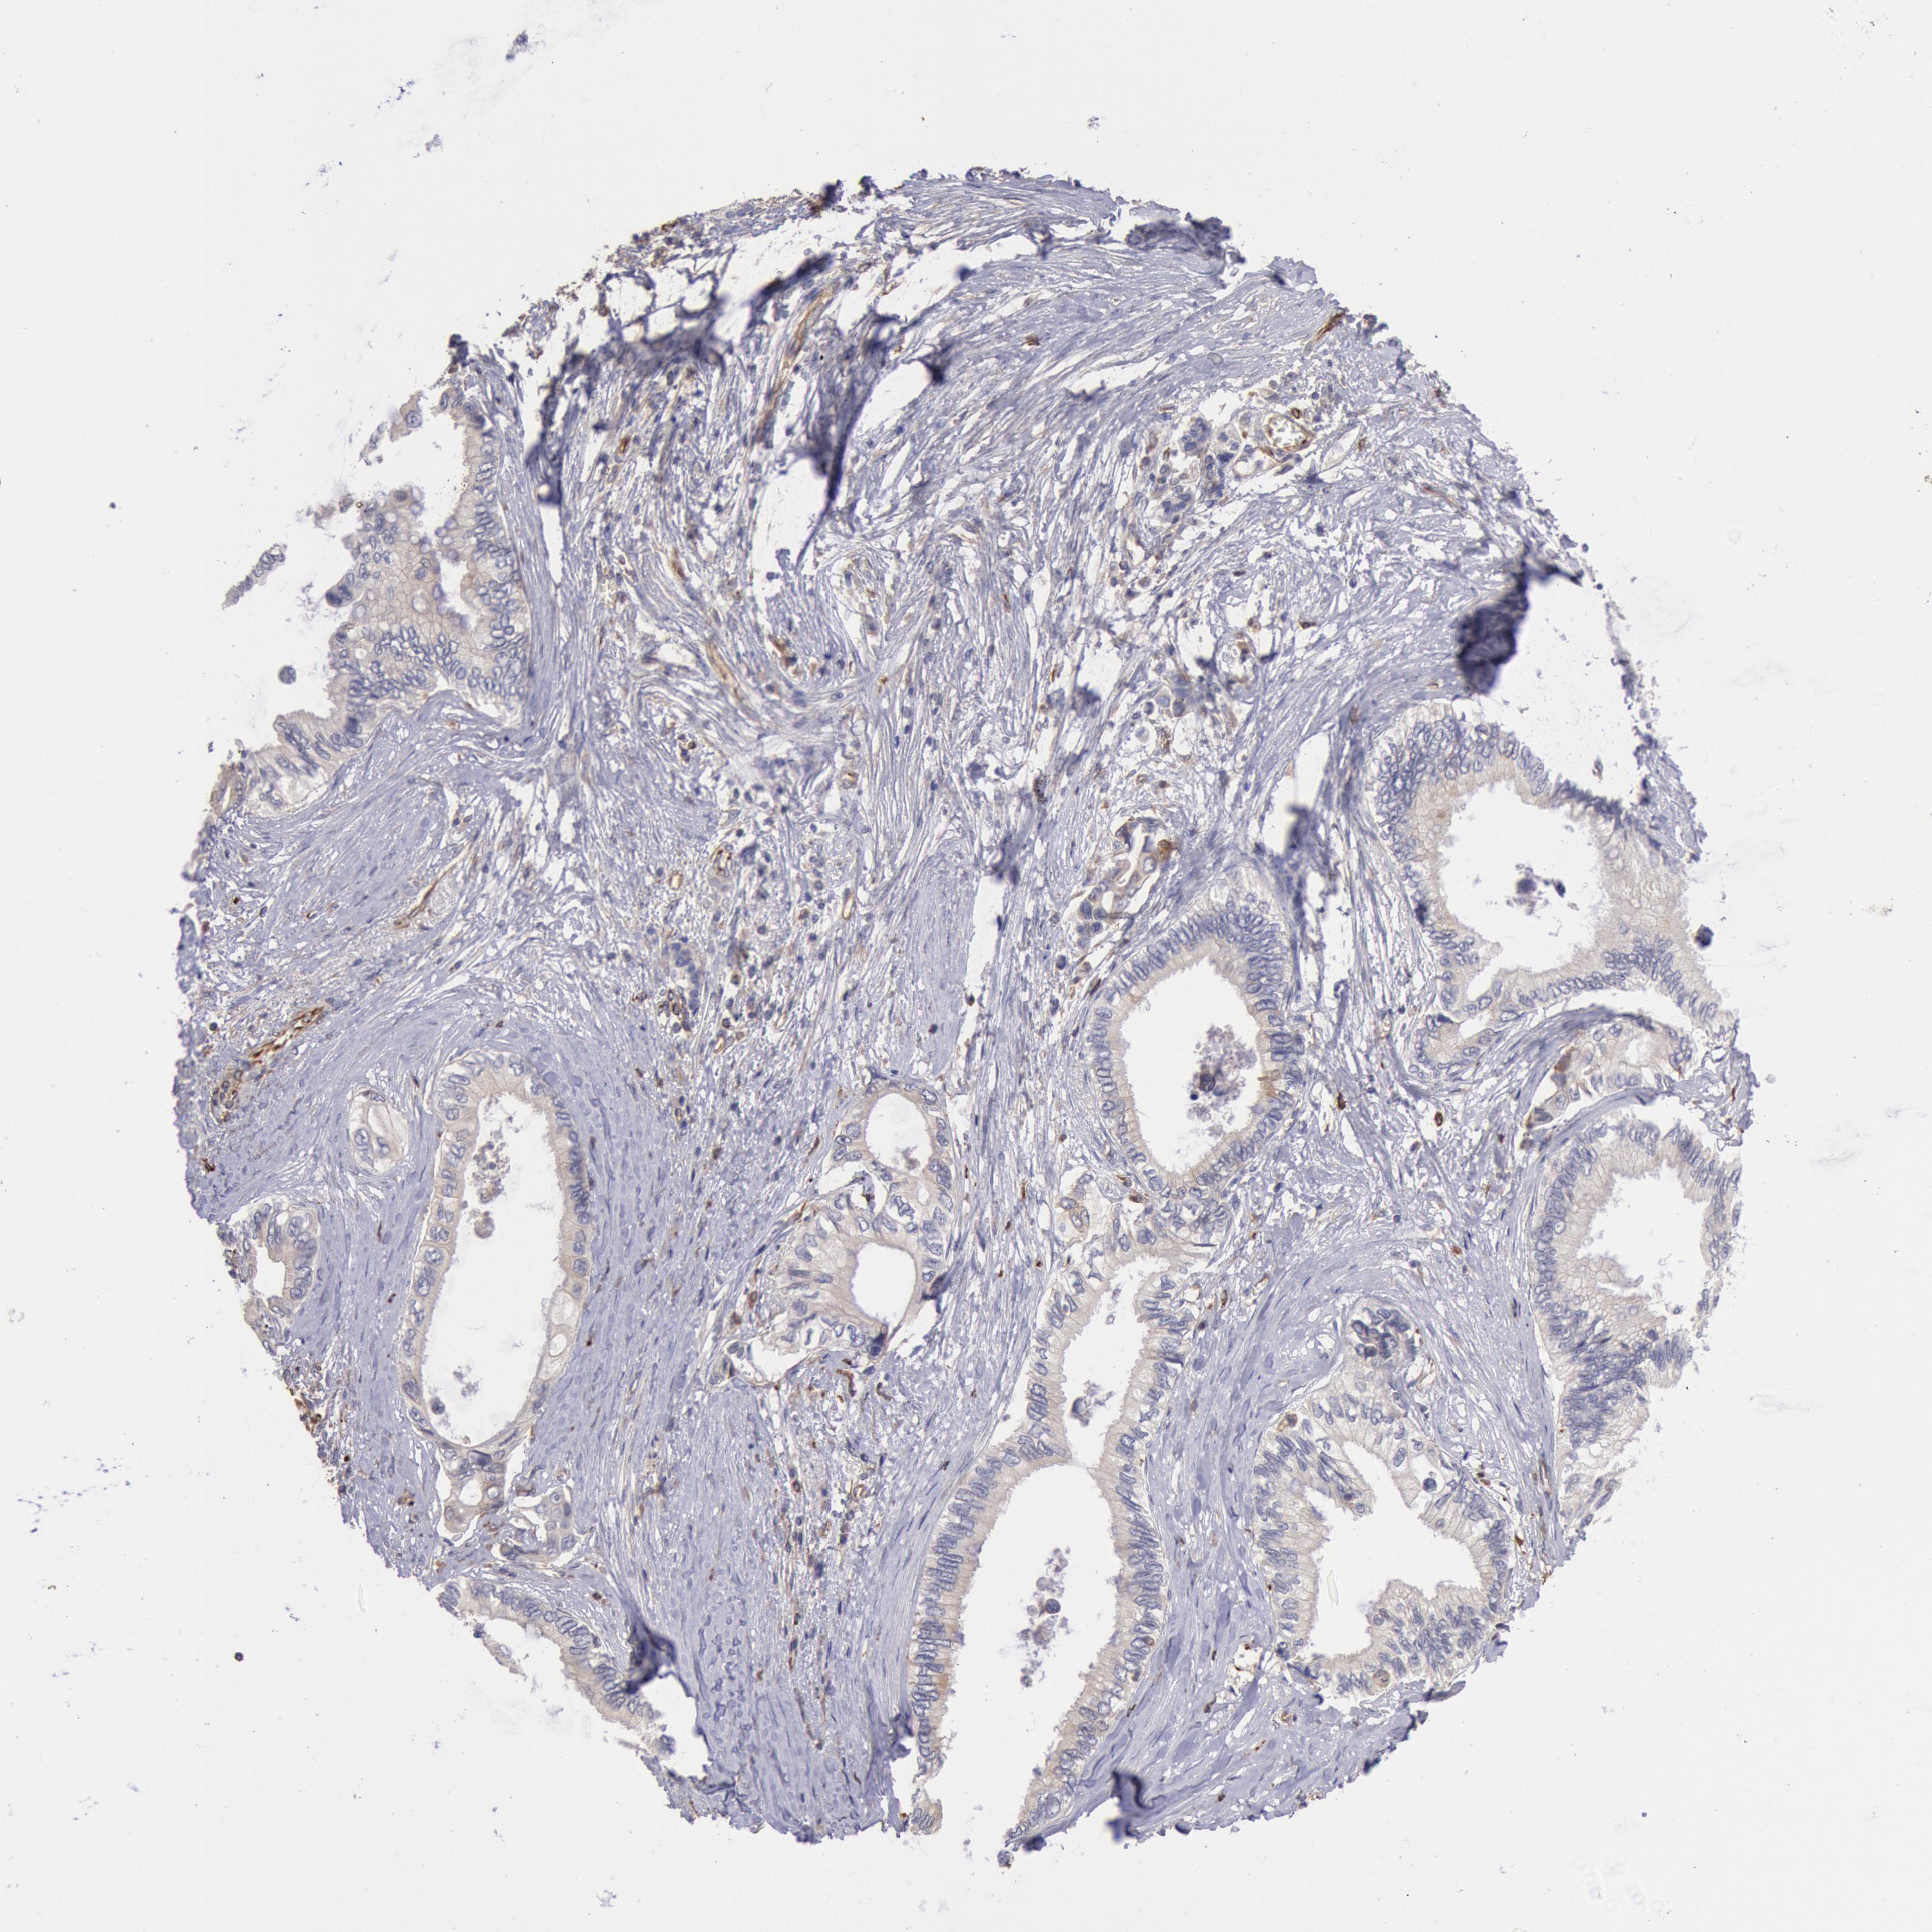

PANCREATIC CANCER - Protein expressioni

A mouse-over function shows sample information and annotation data. Click on an image to view it in a full screen mode. Samples can be filtered based on level of antibody staining by selecting one or several of the following categories: high, medium, low and not detected. The assay and annotation is described here.

Note that samples used for immunohistochemistry by the Human Protein Atlas do not correspond to samples in the TCGA dataset.

Antibody stainingi

Antibody staining in the annotated cell types in the current human tissue is reported as not detected, low, medium, or high, based on conventional immunohistochemistry profiling in selected tissues. This score is based on the combination of the staining intensity and fraction of stained cells.

Each image is clickable and will lead to virtual microscopy that enables deeper exploration of all samples and also displays staining intensity scores, fraction scores and subcellular localization as well as patient and tissue information for each sample.

Antibody HPA001202

Staining

High

Medium

Low

Not detected

Intensity

Strong

Moderate

Weak

Negative

Quantity

>75%

75%-25%

<25%

None

Location

Nuclear

Cytoplasmic/membranous

Cytoplasmic/membranous,nuclear

Adenocarcinoma, NOS